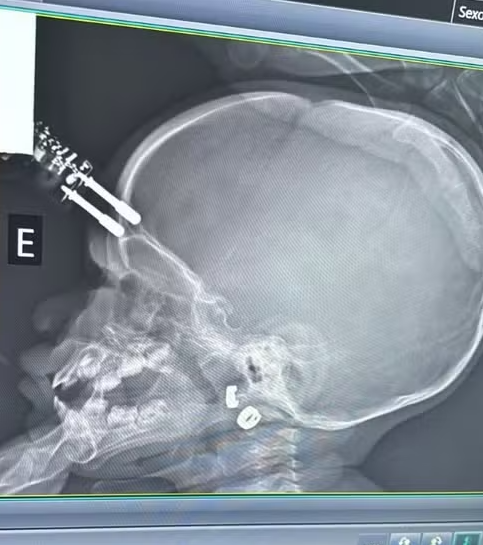

Exames mostram o aparelho que perfurou a a região frontal do crânio

Exames mostram o aparelho que perfurou a a região frontal do crânio Crédito: Arquivo pessoal

Uma bebê de um ano ficou com um carregador cravado na testa após cair da cama, na última terça-feira (13). A mãe da criança foi ao banheiro no momento do acidente, informou o médico que atendeu a menina, Bruno Castro, em entrevista ao G1. O caso aconteceu na cidade de Divinópolis, interior de Minas Gerais.

Ainda segundo ele, a bebê estava com o carregador na mão no momento da queda, o que fez com que o aparelho atingisse a cabeça e perfurasse a região frontal do crânio.